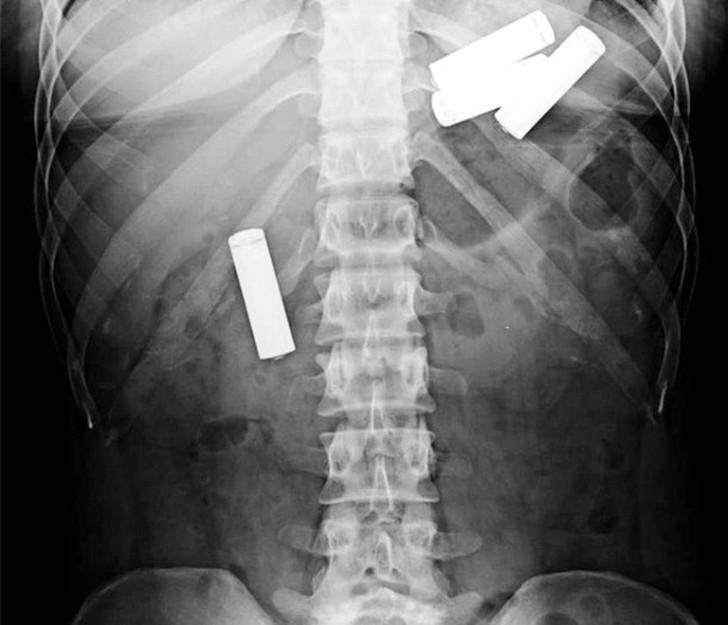

13. А вот и батарейки!